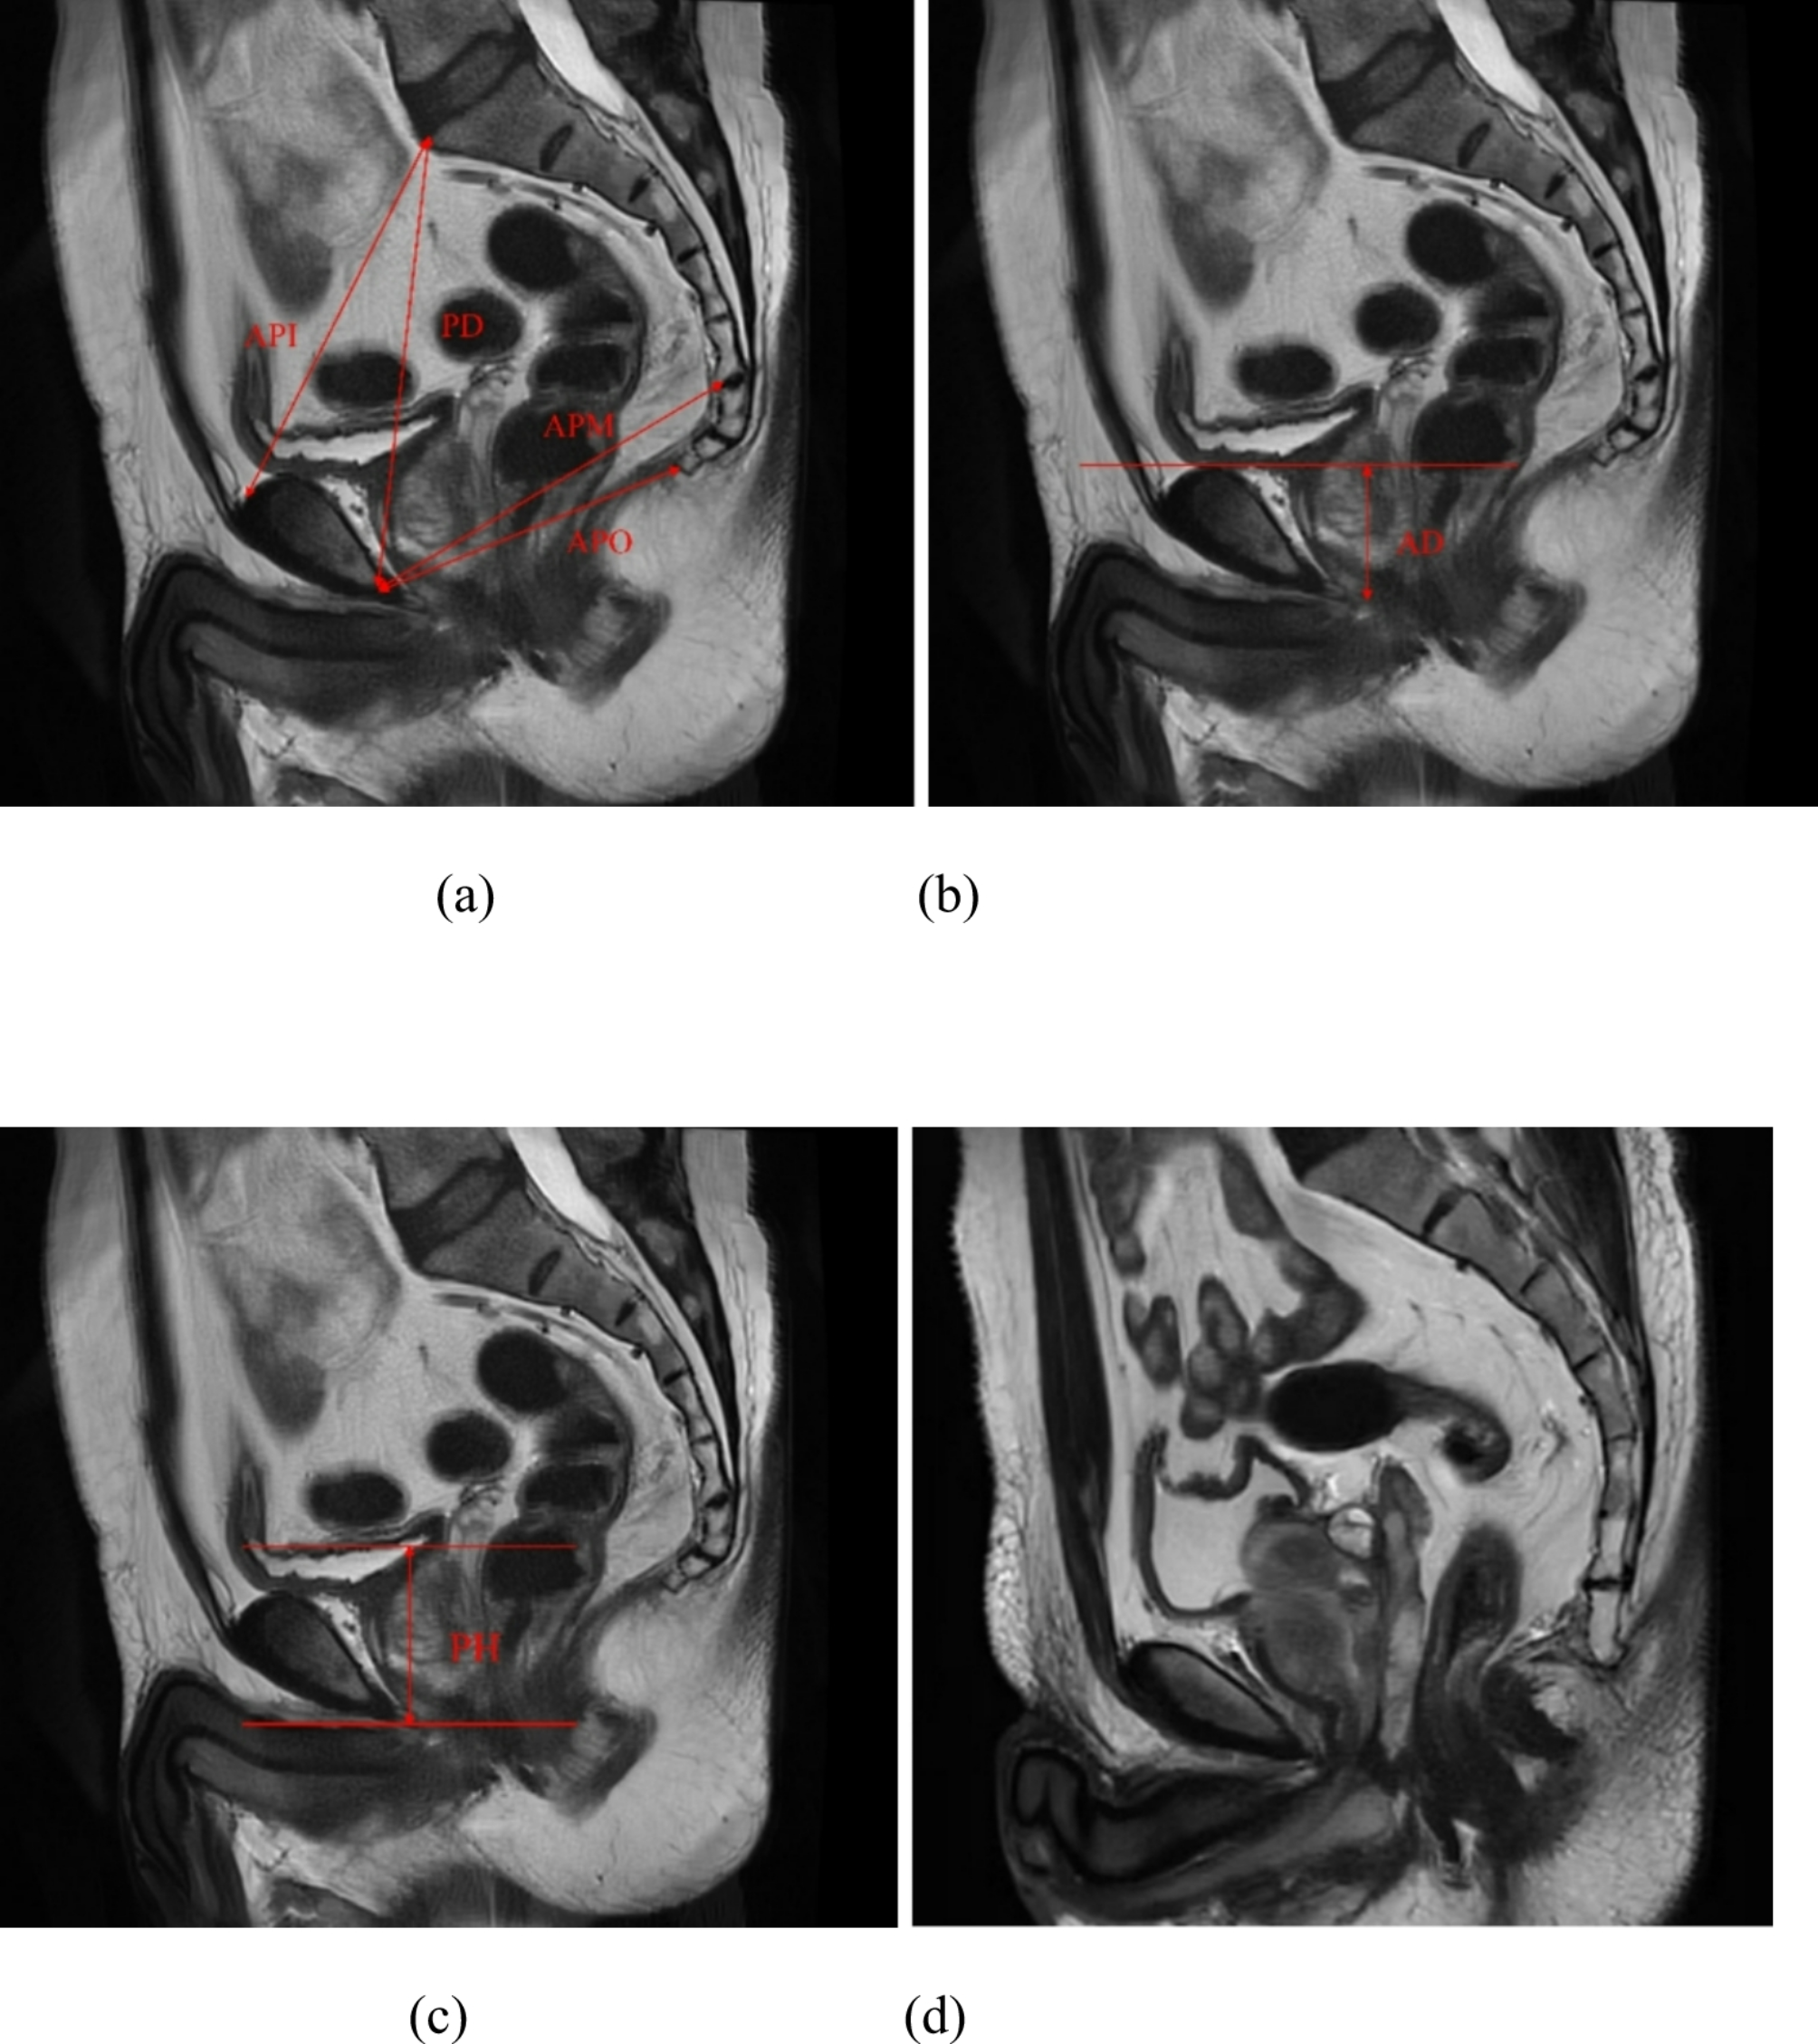

Fig. 2

Sagittal MRI of the pelvis on T2WI. (a) API: anteroposterior distance of the pelvic inlet, the distance from the sacral promontory to the upper edge of the pubic symphysis. APM: anteroposterior distance of the pelvic midplane, the shortest distance from the inferior edge of the pubic symphysis to the sacrococcygeal junction. APO: anteroposterior distance of the pelvic outlet, the distance from the inferior edge of the pubic symphysis to the tip of the coccyx. PD: pelvic depth, the distance from the sacral promontory to the inferior edge of the pubic symphysis. (b) AD: apical depth, the craniocaudal distance from the level of the superior edge of the pubic symphysis to the level of the prostate apex. (c) PH: prostate height, the craniocaudal distance from the level of the superior edge of the prostate to the level of the prostate apex. (d) Presence of median lobe.